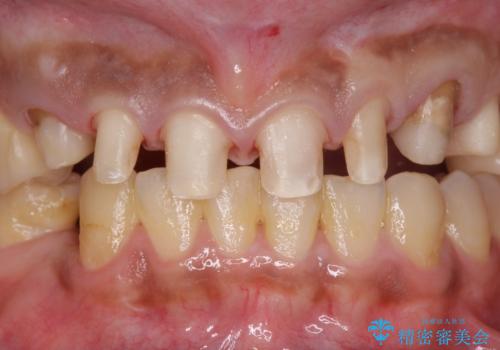

複数箇所コンポジット充填された前歯をセラミック治療

- コンポジットレジンの充填箇所がすり減ってしまい、形の悪くなった前歯の治療を希望され来院されました。

充填部位が大きく、再度充填をするには神経と近くなり抜髄のリスクが高まるため、劣化の少ないセラミックでフルカバーするセラミッククラウン治療を行うこととしました。

前歯の小さな虫歯は、除去したのちコンポジットレジンと言われる樹脂を充填する処置を行うことが多々あります。

しかし、経年劣化が早く着色や小さな虫歯が再発しやすいため、ある程度の大きさになってしまった場合セラミッククラウンで置き替えた方が神経を温存し長期的な予後の期待できる治療となります。